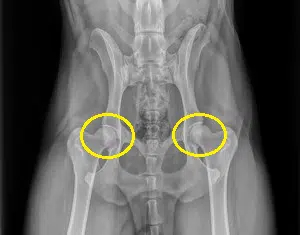

To give you an idea on what happens to your Rottweiler’s body when it develops canine hip dysplasia, let’s familiarize ourselves with what a normal and healthy hip joint looks like.

Circled in yellow are what a dog’s hip joints should normally look like. See how the ball of the leg bones are rounded and fits the shape of the hip socket almost perfectly.